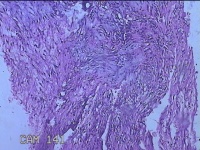

左大腿内侧包块

性别

男

年龄

21岁

临床诊断

脂肪瘤

一般病史

左大腿内侧起包块一月余。

标本名称

大体所见

灰白暗红色包块2.5x2x0.8cm一个,表面糜烂,切开包块呈实性,切面灰白暗红色,质软。